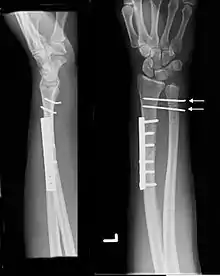

Galeazzi fracture. Arrow points at the dislocated ulnar head | |

The Galeazzi fracture is a fracture of the distal third of the radius with dislocation of the distal radioulnar joint. It classically involves an isolated fracture of the junction of the distal third and middle third of the radius with associated subluxation or dislocation of the distal radio-ulnar joint; the injury disrupts the forearm axis joint.[1]

The dislocation of ulnar head in Galeazzi fracture dislocation may be dorsal (commoner) or volar (rare) depending on the mechanism of injury. If the fall is on the outstretched hand with forearm in pronation, the dislocation is dorsal, and if forearm is in supination at the time of injury, the dislocation is volar.[2]

Galeazzi fractures are best treated with open reduction of the radius and the distal radio-ulnar joint.[3] It has been called the "fracture of necessity," because it necessitates open surgical treatment in the adult.[4] Nonsurgical treatment results in persistent or recurrent dislocations of the distal ulna.[1] However, in skeletally immature patients such as children, the fracture is typically treated with closed reduction.[1]